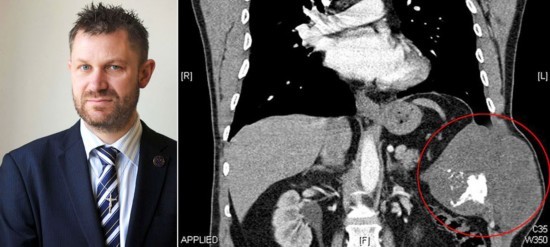

盤點(diǎn)全球各地人體里發(fā)生的詭異事件:英男子體內(nèi)切除三斤重腫瘤 醫(yī)生用水泥補(bǔ)胸